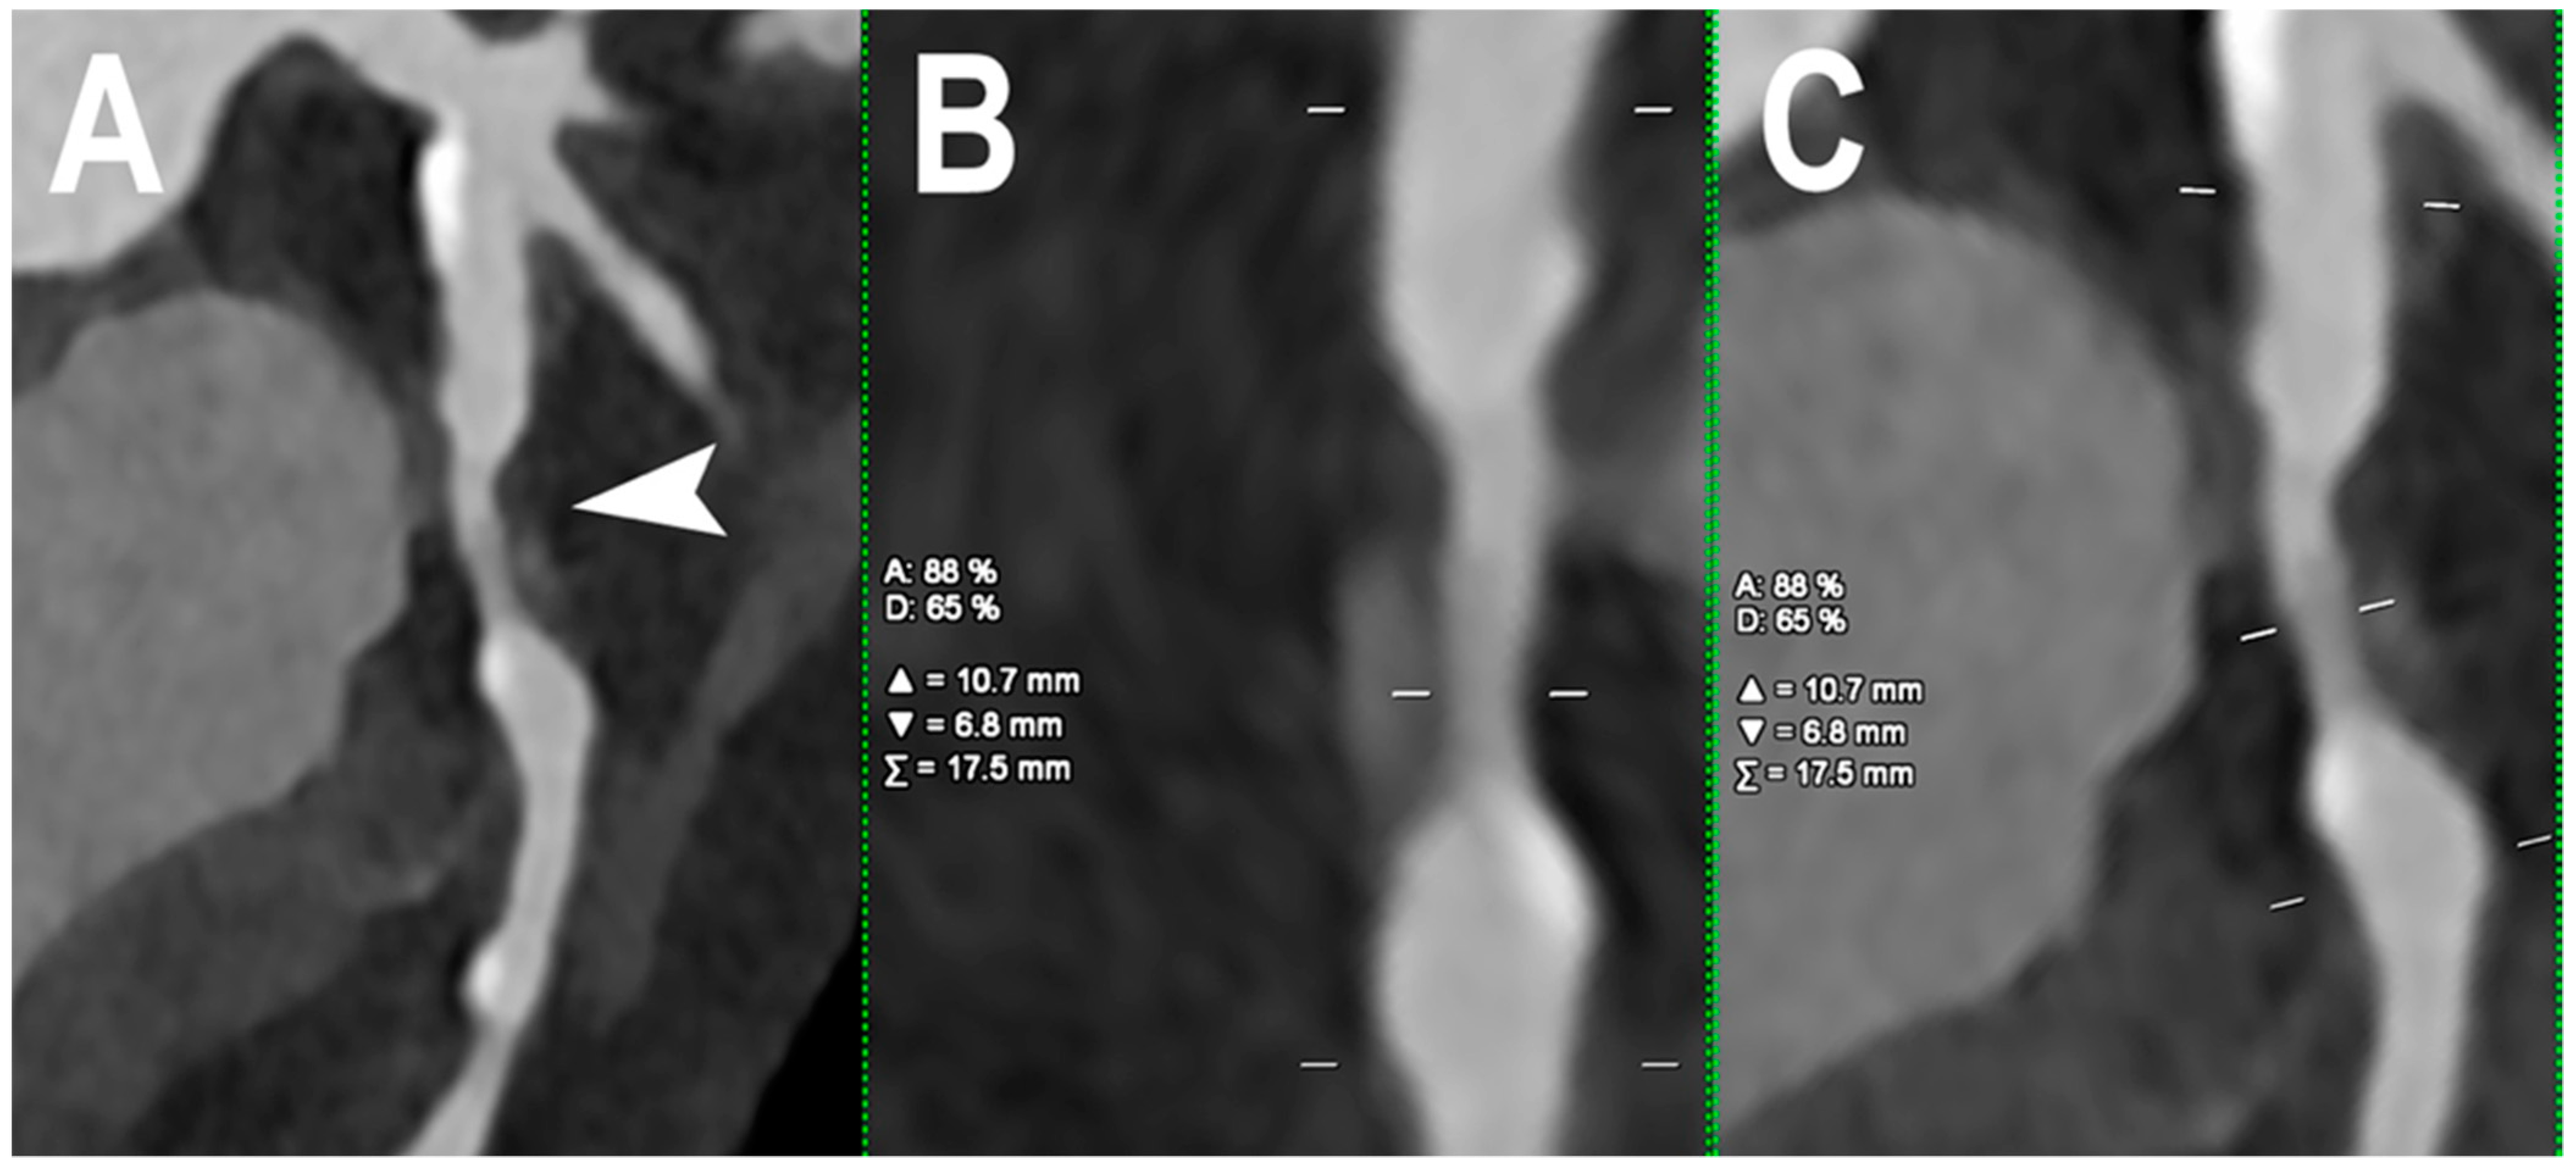

| Koons et al. [12] | 2022 | In vitro | Coronary lumen | PCCT demonstrated an improvement in plaque/lumen delineation and a more accurate stenosis quantification for all plaques than EID-CT. | |

| Allmendiger et al. [32] | 2022 | In vitro | Coronary lumen | An image reconstruction algorithm using PCCT decreases blooming artifacts caused by heavily calcified plaques and improves image interpretability. | |